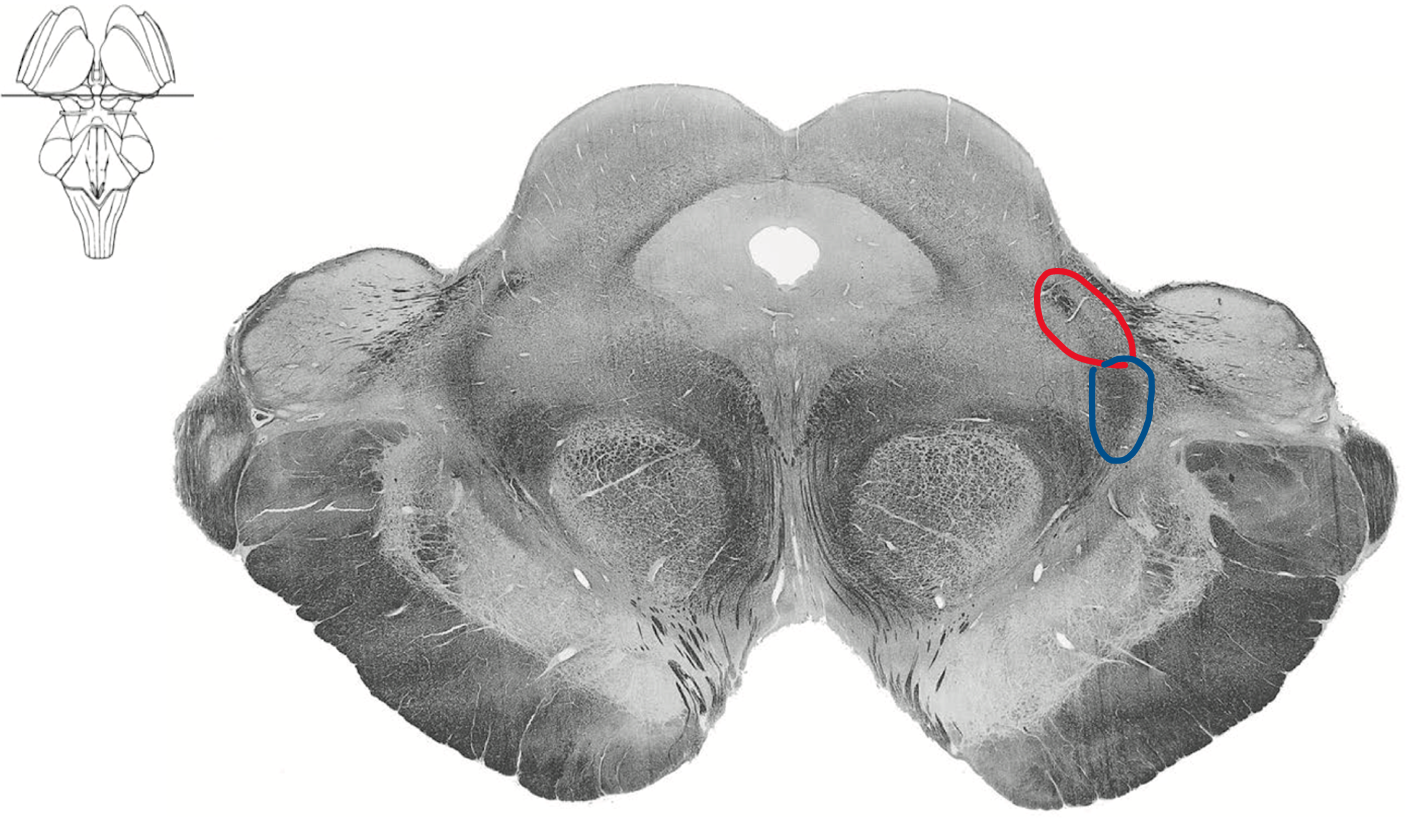

Caudel medulla at Obex (4th ventricle)

Blue medial lemniscus (DCML)

Red ALS spinothalamic tract

Rostral pons

Boomerang

Blue Ventral medial lemniscus (DCML)